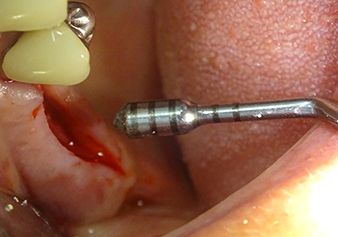

После атравматичной подготовки слизисто-костной оболочки, положение импланта было определено с помощью инструмента I1, далее была проведена подготовка поверхности - до тех пор, пока не возникло первичное сопротивление. Пьезохирургические инструменты были использованы в движении вверх и вниз без оказания давления. Пьезоэлектрическая вибрация создавала необходимую кавитацию.

Затем, с помощью инструмента I2A (диаметр 2,0 мм), дно пазухи перфорировалось периодически и в минимально возможном диапазоне. Этот специфический пьезохирургический метод гарантирует, что мембрана Шнейдера не будет повреждена. При использовании Z25P, мембрана уже была слегка приподнята охлаждающей жидкостью, подаваемой через наконечник инструмента (рис. 3). Во избежание высокого давления в ложе имплантата, количество охлаждающей жидкости составляло не более 50%.